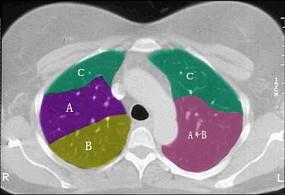

问题 结合肺段模式肺动脉干与右肺动脉层面(见图), 心室层面(见图), 主动脉弓层面(见图), 左右心房层面图(见图),选出左肺下叶的组成 ( )

选项 A、D+E+F+G+H+I+J B、C+D+E+F+G+H+I+J C、F +H+I+J D、E+F+G+H+I+J E、G+H+I+J

答案 C